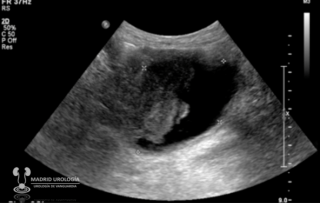

ULTRASONIDO

Constituye uno de los estudios más importantes pues permite el estudio de la pared de la vejiga y nos da alguna información sobre la afección de la vía urinaria superior, aunque en caso de alta sospecha de compromiso de esta, los estudio más relevantes serían el URO TAC o la Urografía Intra Venosa (UIV). Si se detecta una lesión en la vejiga, en principio, no sería necesario la visualización de la misma mediante cistoscopia para proceder a la Exploración Vesical Bajo anestesia.

![]() |

| Ultrasonido en el que se muestra lesión vesical exofítica. |